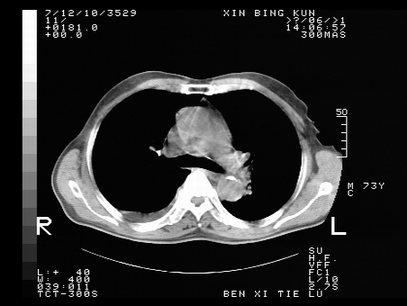

标题: CT10820:男,73岁,病史肺TB,现病史肺炎,直肠CA术后 [打印本页]

标题: CT10820:男,73岁,病史肺TB,现病史肺炎,直肠CA术后

双肺间质改变,依据病史双肺多发结节灶考虑转移,少量胸水.

1.两肺结核.2.两肺多发转移瘤.3右侧少量胸腔积液4.主动脉钙化.

双肺多发结节及条片状致密影,右侧少量胸腔积液。临床:直肠ca术后,肺tb病史。综合考虑:1 双肺转移!2 继发性肺结核合并感染!

此人病史较复杂,原有肺结核,直肠癌术后。肺部病灶形态亦呈多形性。因此,不可仅以一种病来解释肺部的病变。双肺多发的类圆形结节灶,结合病史还是首先考虑转移瘤,而双肺其余病灶还需结合化验室检查,结核或肺部感染在无其它检查资料的情况下不好排除。还是那句话----放射科医生不是开照像馆的,我们也是医生,看片一定要多结合临床及其它检查资料。要当一名合格的放射科医生,并不比当一名临床医生容易,我们可别把自已不当医生看。

两肺多发结节影,并见滋养动脉与其相连,考虑 两肺转移. 右侧胸腔积液考虑胸膜转移.

左肺上叶下叶背段,右肺中下叶见多发斑片状、条索状高密度影,兵变周围小结节影形成“树芽”样改变。 左肺上叶舌段近前胸壁处及右肺中叶内侧段见结节影。右侧胸膜腔内见液体密度区。纵隔内未见明确增大淋巴结。考虑左肺上叶舌段近前胸壁处及右肺中叶转移瘤可能性大。两肺继发型肺结核。右侧胸腔积液。